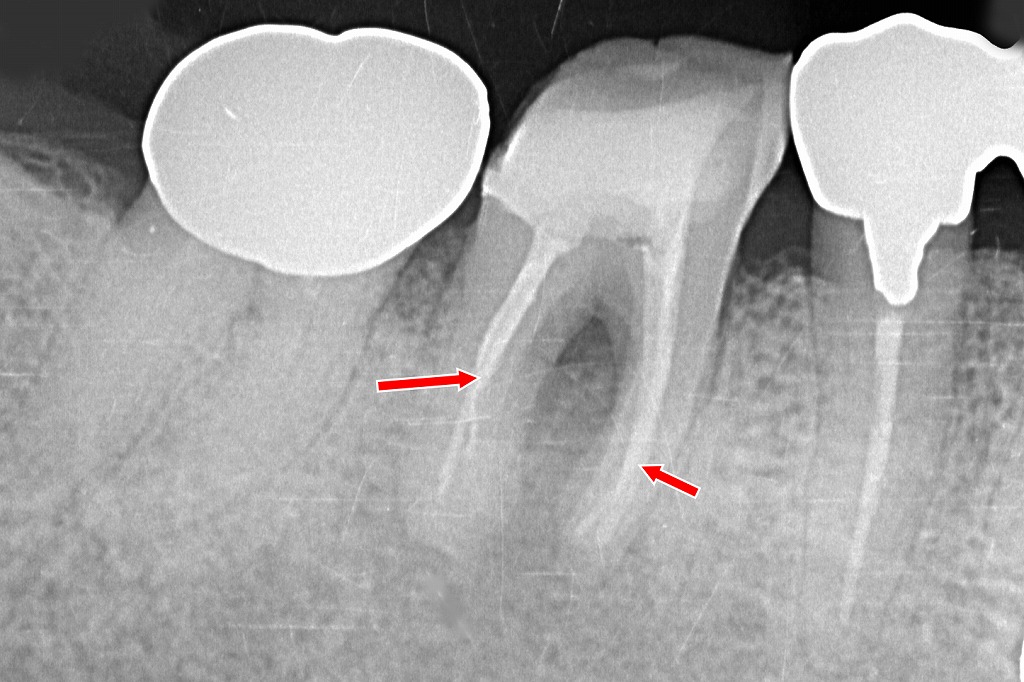

根管充填材が根尖付近まで適切に到達

赤い矢印で示された領域では、根管内が均一な不透過像(白い充填材)で満たされており、根尖(根の先端)までしっかり届いています。

これは根管治療が適切に完了している重要な指標です。

根分岐部までしっかり清掃・充填

この歯は**根が2つに分かれるタイプ(近心根の二根)**で、根管形態が複雑になりやすい部位です。

画像からは、各根管が独立して適切に充填されていることが読み取れます。

周囲骨に急性の透過像はなし

根尖部の骨には、治癒の妨げとなるような**明らかな透過像(黒い病変)や膿の溜まり(根尖病変)**は確認されません。

治療が適切に行われ、炎症の鎮静化が期待できる状態と言えます。

再感染のリスクを抑える密なシール

根管充填材の緻密性が保たれており、

「隙間がない → 細菌が入りにくい」

という、再感染予防に重要な条件が満たされています。